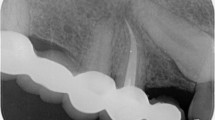

Patients over the age of 16 with radiographic evidence of apical periodontitis and a diagnosis of pulpal necrosis confirmed by negative response to hot and cold tests were randomised to receive either a one or two visit root canal treatment (RoCT).

Two hundred and eighty-seven patients (300 teeth) were randomised. One hundred and fifty-five teeth were allocated to the single visit group and 145 to two-visit treatment. Eighteen teeth were lost to follow up, nine from each group. At two years there were no significant differences between the groups, with 96.57% (141 of 146 teeth) in the single-visit group being classified as healed compared with 88.97% (121 of 136 teeth) in the two-visit group.

This study provided evidence that a meticulously instrumented single-visit root canal treatment can be as successful as a two-visit treatment. There was no significant difference in radiographic evidence of periapical healing between single-visit and two-visit root canal treatment.